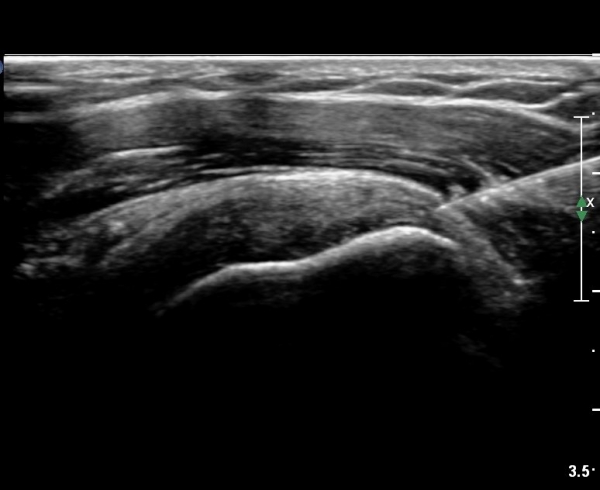

ÃÊÀ½ÆÄ ¼Ò°ß :  È¸Àü±Ù°³°£°Ý(rotato cuff interval) ³»Ãø °Ë»ç»ó  »óºÎ °ß°©Çϱٰǿ¡ ƯÀÌ ¼Ò°ß º¸ÀÌÁö ¾ÊÀ½(»çÁø 1).